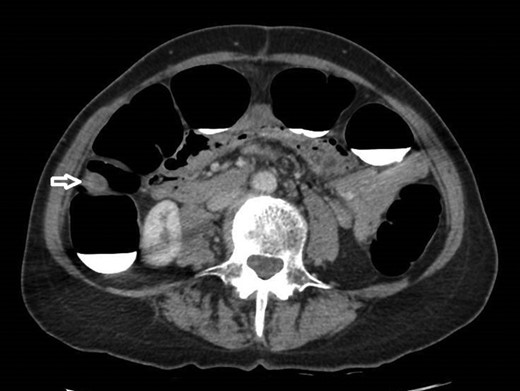

12 mm polypoidal mass (white arrow) visible on sagittal image of post-contrast CTVC.

In view of this CT Colonoscopy was performed, alongside a CT Chest examination. This showed a 12 mm lesion arising from the lateral wall of the ascending colon. It appeared rounded and mural-based, and displayed irregular peripheral enhancement post-contrast. It did not conform with a lipomatous lesion, with an average internal density of approximately 40 HU. No other colonic lesions were demonstrated, and no locoregional adenopathy or distant metastases were identified.